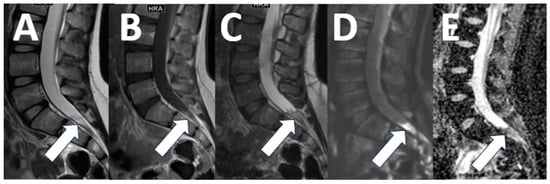

Spondylolysis is a common cause of back pain in children and adolescents, found in 12–16% [18]. The diagnosis of spondylolysis is made by radiography and computed tomography (CT) imaging [18]. However, early signs of spondylolysis, such as pedicle edema, are not apparent on CT but can be detected with MR imaging. Detection of pedicle edema from spondylolysis can help establish a diagnosis early and avoid the need for radiographs and CT imaging, which require exposing patients to ionizing radiation [20]. Our contextualized MRI protocol for lumbar back pain includes standard sequences for the evaluation of intervertebral discs and neural foramina and a sagittal T2-weighted sequence with fat suppression (STIR) to detect pedicle edema, as well as a 3D T1-weighted sequence for assessing integrity of the pars articularis (Table 2) (Figure 4).

Figure 4. Spondylolysis. (A) A 12-year-old female with back pain. The sagittal T2-weighted image with fat saturation shows left-sided pedicle edema ((A), arrow). (B,C) A 14-year-old female, competitive swimmer with back pain. Sagittal 3D T1 imaging shows anterolisthesis of L5 on S1 ((B), arrow) as well as a corticated fracture of the L5 pars articularis consistent with spondylolysis ((C), arrow).